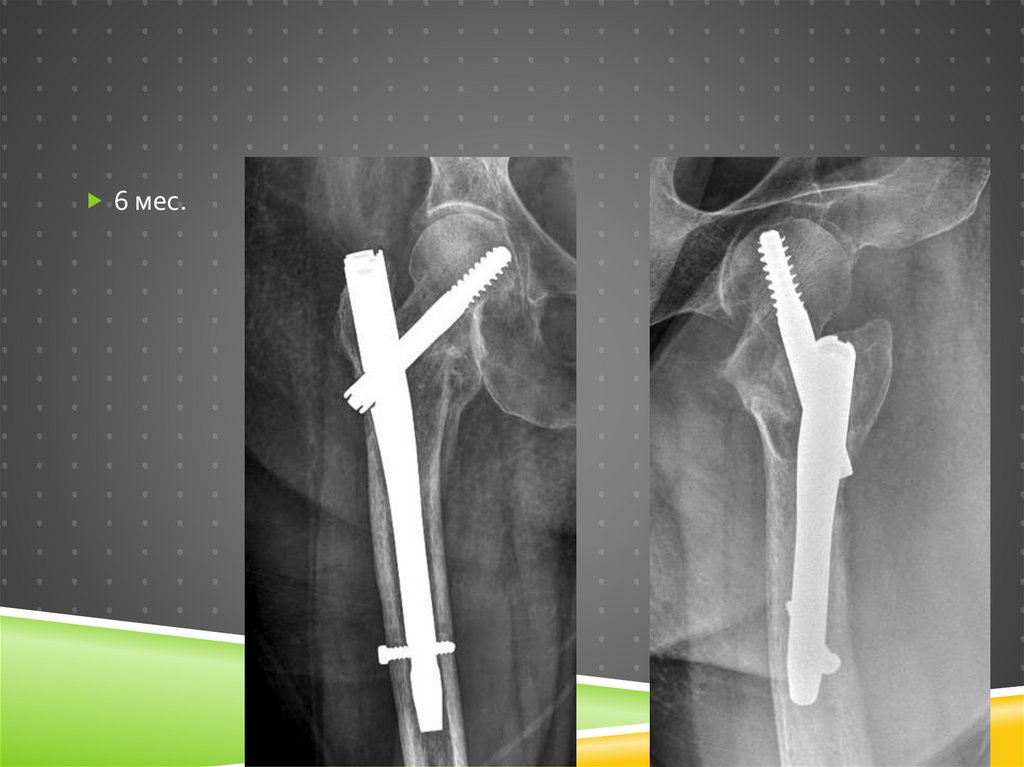

68. 6 мес.

6 МЕС.

68